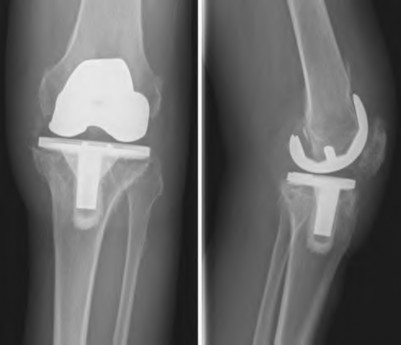

Question 12

When planning a medial opening wedge high tibial osteotomy (HTO) for isolated medial compartment osteoarthritis in a varus knee, the surgeon intends to shift the mechanical axis to the Fujisawa point. Where is the Fujisawa point located on the tibial plateau?

During a revision total knee arthroplasty, removal of the tibial component reveals a massive contained metaphyseal defect measuring 3 cm deep, but with an intact cortical rim. According to the Anderson Orthopaedic Research Institute (AORI) classification, what type of defect is this, and what is the preferred method of management?

Explanation

When evaluating a patient for a Unicompartmental Knee Arthroplasty (UKA), which of the following is considered a classic absolute contraindication?

A 52-year-old male with isolated medial compartment osteoarthritis is evaluated for a unicompartmental knee arthroplasty (UKA).

Which of the following conditions is considered a strict contraindication to a traditional mobile-bearing UKA?

Question 82

Which of the following is traditionally considered an absolute contraindication to a fixed-bearing medial unicompartmental knee arthroplasty (UKA)?